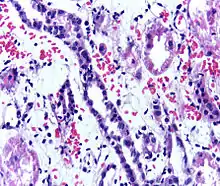

People with ESRD who receive a kidney transplant generally live longer then people with ESRD who are on dialysis and may have a better quality of life.[1] However, kidney transplant recipients must remain on immunosuppressants (medications to suppress the immune system) for the rest of their life to prevent their body from rejecting the new kidney.[1] This long-term immunosuppression puts them at higher risk for infections and cancer.[3] Kidney transplant rejection can be classified as cellular rejection or antibody-mediated rejection. Antibody-mediated rejection can be classified as hyperacute, acute, or chronic, depending on how long after the transplant it occurs. If rejection is suspected, a kidney biopsy should be obtained.[3] It is important to regularly monitor the new kidney's function by measuring serum creatinine and other labs; this should be done at least every three months for the rest of the person's life.[3]

Immunosuppressant drugs are used to suppress the immune system from rejecting the donor kidney. These medicines must be taken for the rest of the recipient's life. The most common medication regimen today is a mixture of tacrolimus, mycophenolate, and prednisolone. Some recipients may instead take ciclosporin, sirolimus, or azathioprine. The risk of early rejection of the transplanted kidney is increased if corticosteroids are avoided or withdrawn after the transplantation.[54] Ciclosporin, considered a breakthrough immunosuppressive when first discovered in the 1980s, ironically causes nephrotoxicity and can result in iatrogenic damage to the newly transplanted kidney. Tacrolimus, which is a similar drug, also causes nephrotoxicity. Blood levels of both must be monitored closely and if the recipient seems to have declining kidney function or proteinuria, a kidney transplant biopsy may be necessary to determine whether this is due to rejection [55][56] or ciclosporin or tacrolimus intoxication .

Acute rejection occurs in 10–25% of people after transplant during the first 60 days. Rejection does not necessarily mean loss of the organ, but it may necessitate additional treatment and medication adjustments.[63]

Complications

- Transplant rejection (hyperacute, acute or chronic)[64]

- Postoperative bleeding following kidney transplant as seen on ultrasound[67]

Postoperative bleeding following kidney transplant as seen on ultrasound[67]